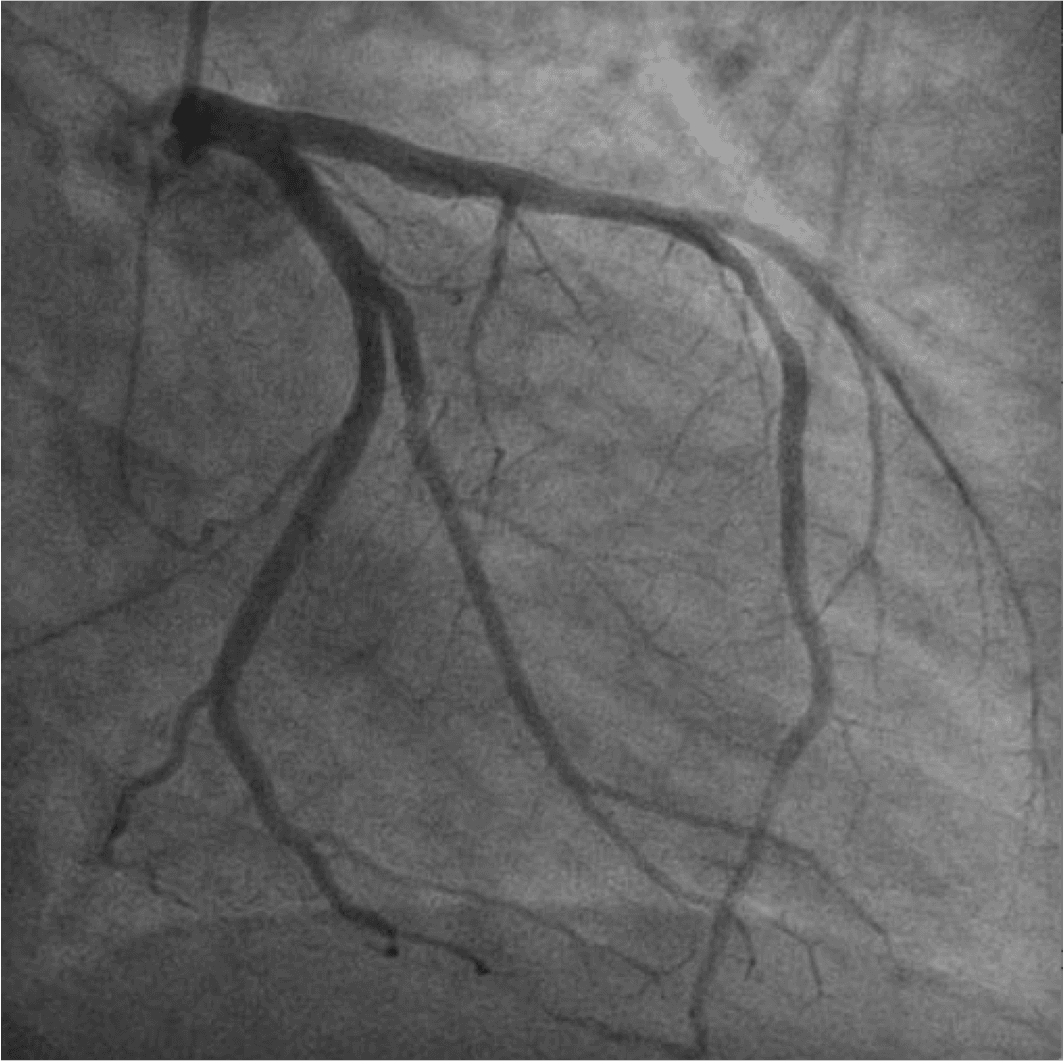

Em pacientes uniarteriais, a realização de testes não invasivos permite determinar o significado funcional da estenose coronária e correlacionar com a angiografia de forma simples e acurada.

Apesar do desenvolvimento crescente dos métodos de imagem não invasivos, a resolução temporal e espacial da coronariografia permanece como o padrão ouro para guiar revascularização.